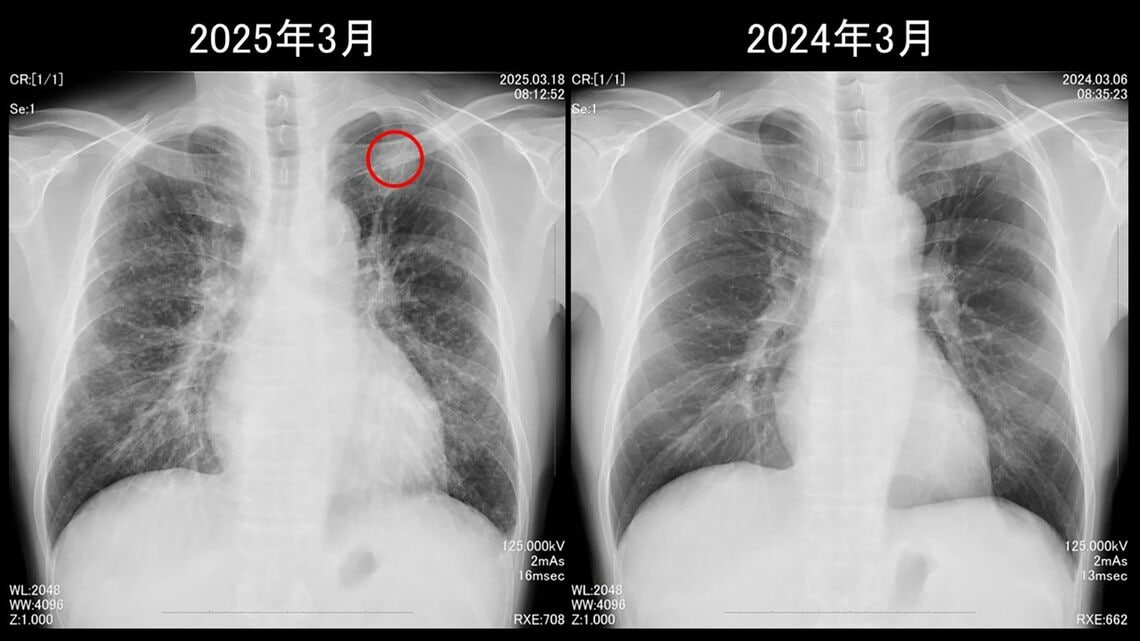

肺のX線写真

松田さんの肺のX線写真。赤丸で囲っているところががん。そのほか肺全体に白い斑点が見えるのが転移だという。いずれも1年前には見つからなかった(画像:松田さん提供)